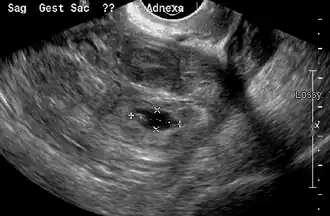

An ultrasound showing a gestational sac with the fetal heart in the fallopian tube has a very high specificity for ectopic pregnancy. It involves a long, thin transducer, covered with the conducting gel and a plastic/latex sheath and inserted into the vagina.[38] Transvaginal ultrasonography has a sensitivity of at least 90% for ectopic pregnancy.[5] The diagnostic ultrasonographic finding in ectopic pregnancy is an adnexal mass that moves separately from the ovary. In around 60% of cases, it is an inhomogeneous or a noncystic adnexal mass, sometimes known as the "blob sign". It is generally spherical, but a more tubular appearance may be seen in the case of hematosalpinx. This sign has been estimated to have a sensitivity of 84% and a specificity of 99% in diagnosing ectopic pregnancy.[5] In the study estimating these values, the blob sign had a positive predictive value of 96% and a negative predictive value of 95%.[5] The visualization of an empty extrauterine gestational sac is sometimes known as the "bagel sign", and is present in around 20% of cases.[5] In another 20% of cases, there is visualization of a gestational sac containing a yolk sac or an embryo.[5] Ectopic pregnancies where there is visualization of cardiac activity are sometimes termed "viable ectopic".[5]

Transvaginal ultrasonography of an ectopic pregnancy, showing the field of view in the following image -

A "blob sign", which consists of the ectopic pregnancy. The ovary is distinguished from it by having follicles, whereof one is visible in the field. This patient had an intrauterine device (IUD) with progestogen, whose cross-section is visible in the field, leaving an ultrasound shadow distally to it. -

Ultrasound image showing an ectopic pregnancy where a gestational sac and fetus have been formed